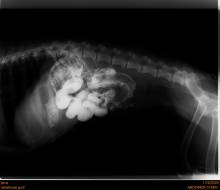

Prix d'une échographie pour chien à vers Luneray proche de Dieppe